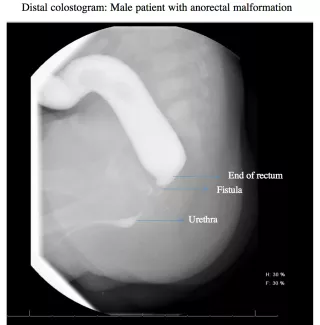

Before the second operation, where an anal opening will be made in the correct location, within the anal sphincter, your child may need to have a radiographic study called a distal colostogram to help prepare for surgery. The study helps to determine the distance from the blind end of the rectum to the skin and if there is a fistula.

If a fistula is found to the urogenital system, it will be closed at the time of the second operation. The stoma will be left intact, and not closed, to allow the new anus to heal. After this operation, the baby can go home to recover.